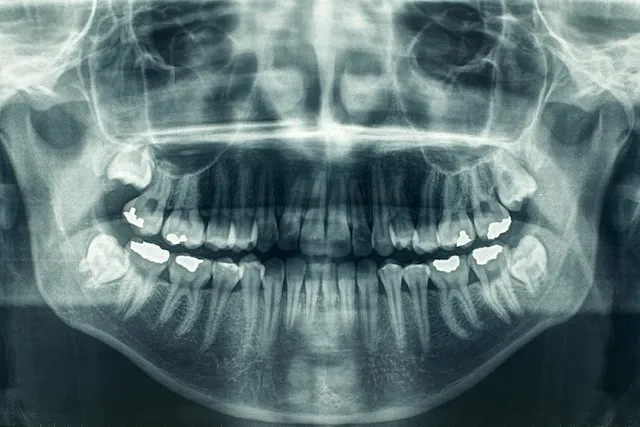

Radiografias dentais

Radiografias dentais Raios-X dentais podem detectar problemas logo no início em sua boca, dentes, gengivas e osso da maxila e mandíbula. Tratar os problemas antes que se tornem sérios pode economizar dinheiro, dor e, às vezes, até sua vida. O que são raios-X dentais e por que são necessários? Na lista de suas coisas favoritas, […]